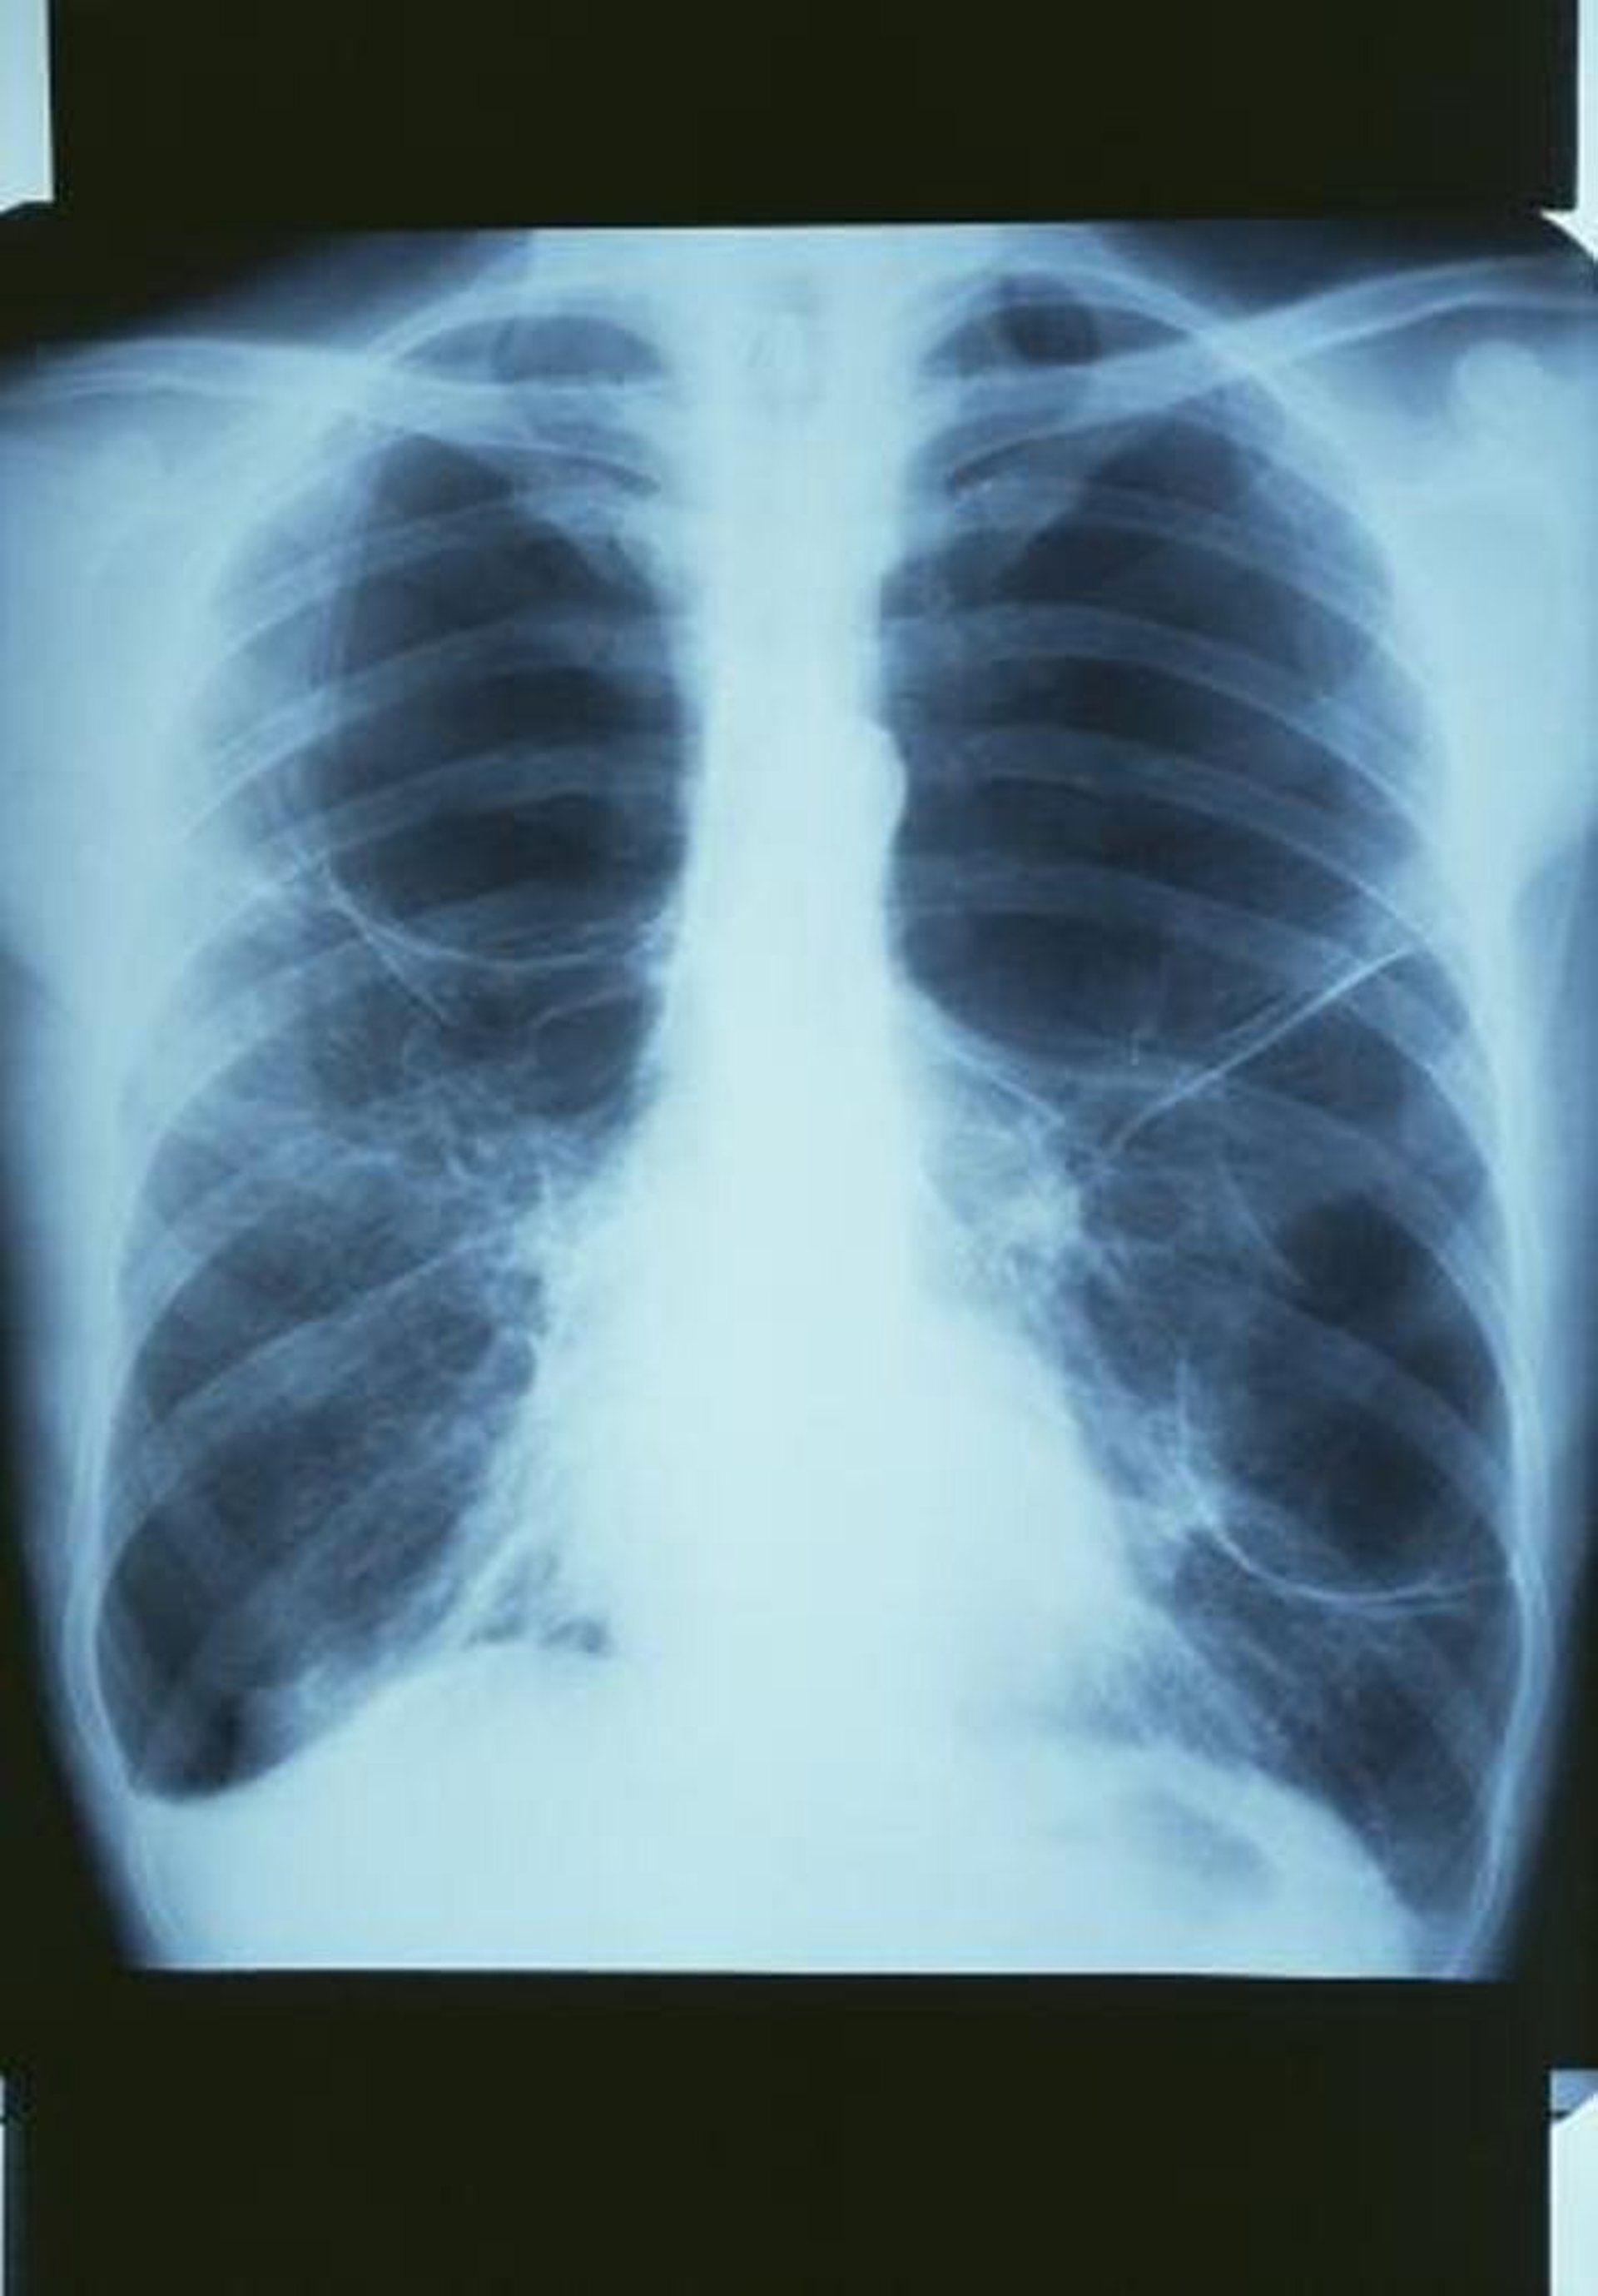

COPD có túi khí

Phim X-quang phổi cho thấy một túi khí lớn ở phía trên phổi bên phải và 2 túi khí lớn ở phổi trái.

GJLP/CNRI/THƯ VIỆN HÌNH ẢNH KHOA HỌC